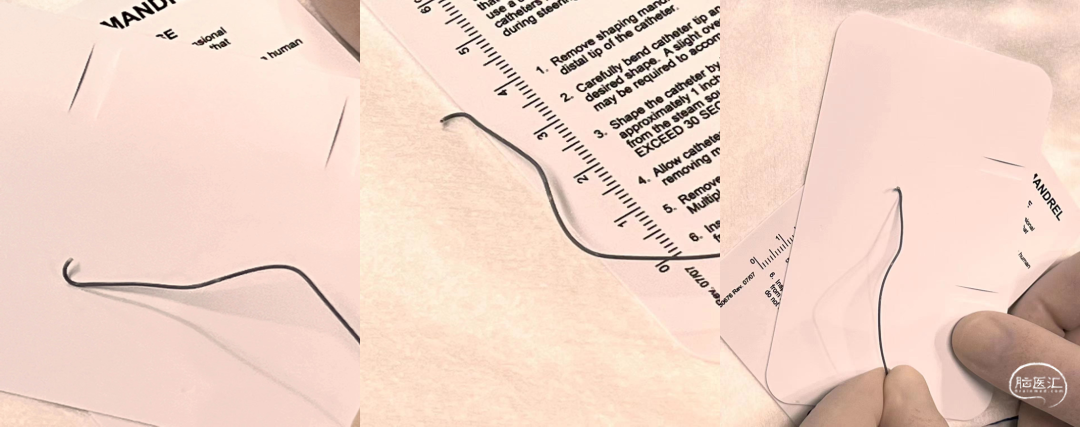

微导管塑形

微导管塑形时1:2蒸汽塑形形态

微导管塑形后形态